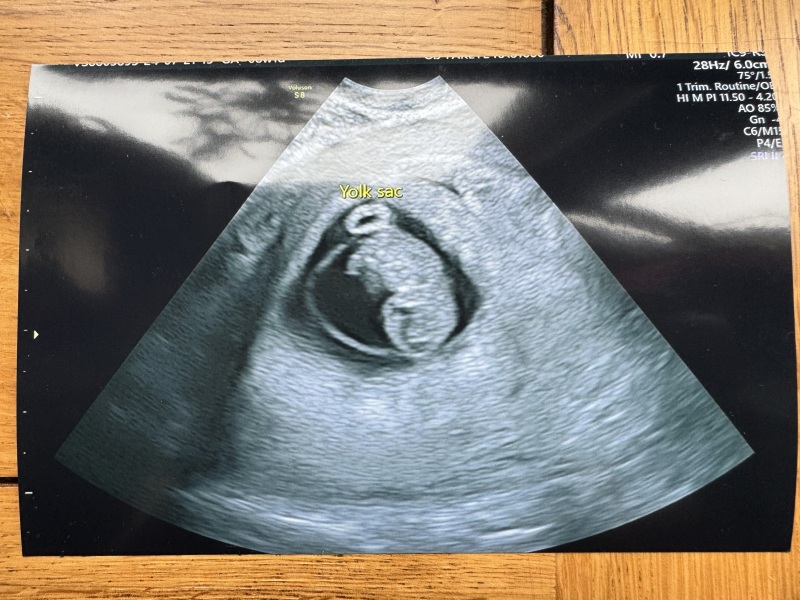

So so happy to say everything is looking great! We saw the little bean with a really strong heartbeat. Measuring my 8+1 dates exactly which is very reassuring. Baby is about 16mm. Got a wee scan pic too and I can’t believe how much they’ve grown since my scan 10 days ago! You can see little limb nubs and everything 🄹

@purplecolouroffunk such wonderful news and what an amazing picture! So happy for you Purple šŸ’œ xxx

jellyfish2 · 21/07/2024 17:56

@purplecolouroffunk amazing! I'm so happy all was well 🄰 what a great picture too šŸ˜

That’s such a beautiful picture @purplecolouroffunk 🄰

That's a beautiful picture @purplecolouroffunk I'm so glad for you.